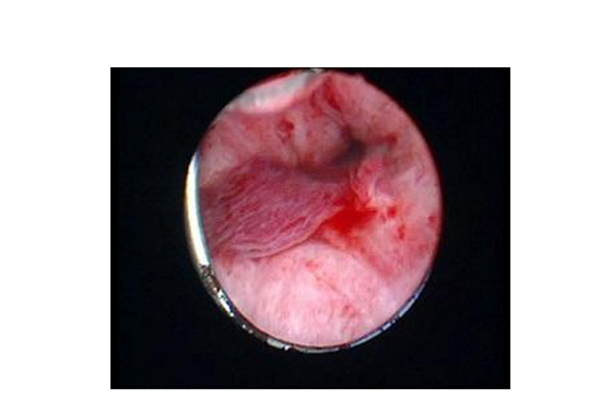

子宮頸糜爛圖片

宮頸糜爛 (8)

宮頸糜爛 (9)

宮頸糜爛 (56)

宮頸糜爛 (57)

宮頸糜爛 (58)

宮頸糜爛 (59)

宮頸糜爛 (6)

宮頸糜爛 (60)

宮頸糜爛 (7)

宮頸糜爛 (40)

宮頸糜爛 (41)

宮頸糜爛 (42)

宮頸糜爛 (43)

宮頸糜爛 (44)

宮頸糜爛 (45)

宮頸糜爛 (46)

宮頸糜爛 (47)

宮頸糜爛 (48)

宮頸糜爛 (49)

宮頸糜爛 (5)